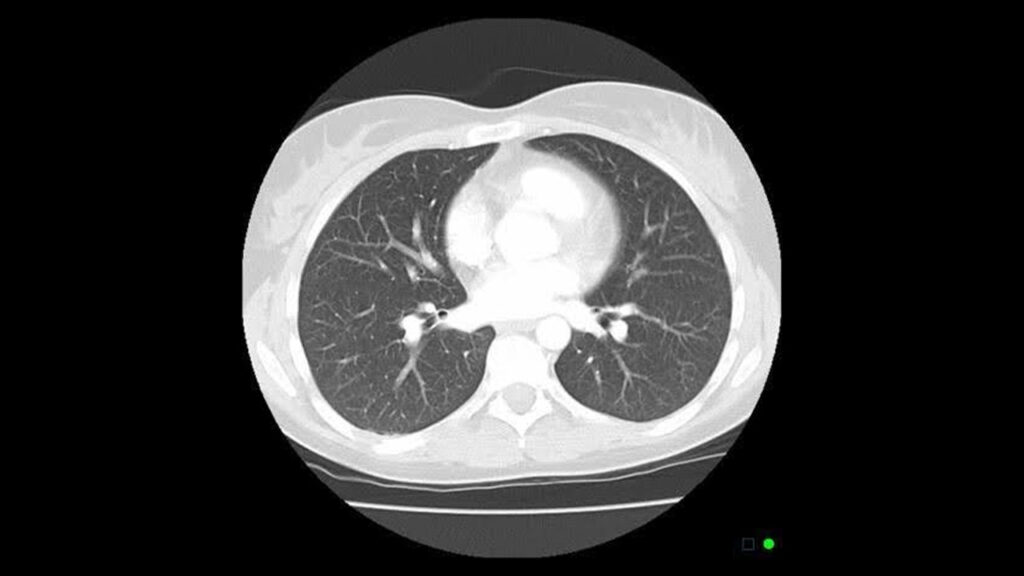

Lung cancer screening uses a low-dose computed tomography (LDCT) scan to look for early signs of lung cancer in people at high risk. Unlike a chest X-ray, LDCT can detect small lung nodules that may represent early cancer, often years before symptoms develop.

- Non-invasive

- No needles or contrast dye

- Takes less than 5 minutes

- Uses significantly lower radiation than a standard CT scan